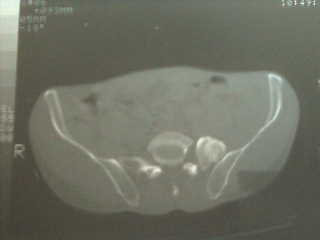

以下是引用sdqzwyx在2006-12-6 13:22:00的发言:[br]图片不全,考虑腰5不完全骶化(腰5左侧横突肥大与骶骨形成关节),定位像应该很明确的。

以下是引用乡医在2006-12-6 14:55:00的发言:[br]腰5左侧横突肥大,属发育变异。

以下是引用一棵树在2006-12-6 13:13:00的发言:[br]腰5左侧横突肥大(比较常见)